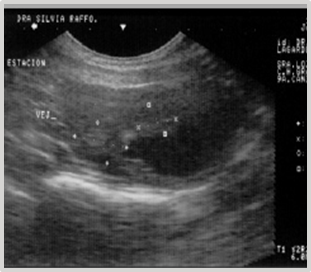

The medical treatment initiated for over two months fails to yield a favorable outcome. The diagnosis is reassessed. Contrast radiography and ultrasonography are requested. The reports indicate an irregularly shaped image, fixed to the ventral fundic wall, non-infiltrative, granular in appearance, with a diameter of 2.28 cm x 1.23 cm, compatible with a neoplasm (Figure 27).

Figure 27 Pneumocystography and ultrasonography indicate an irregular image of 2.28 cm x 1.23 cm, fixed to the ventral fundic wall of the bladder.